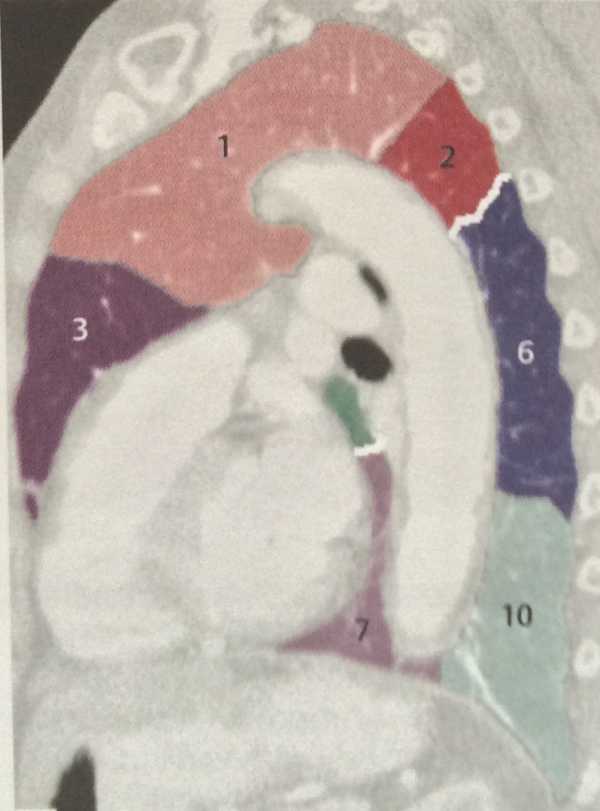

Анатомические изображения сегментов легких различных животных

Раздел: Другие животные